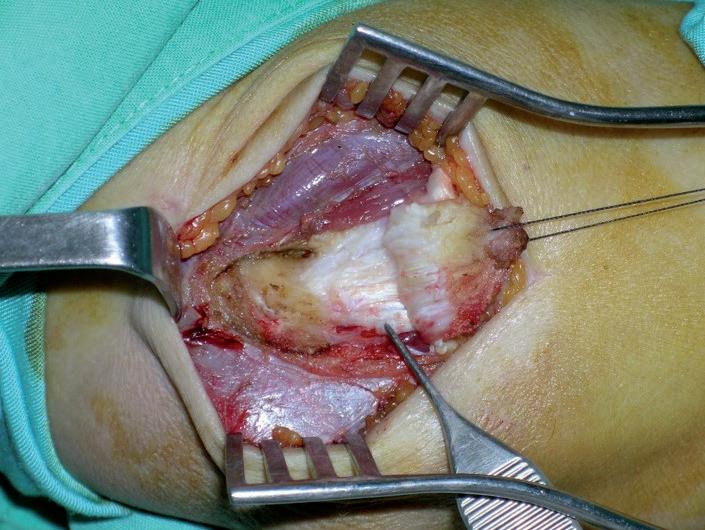

Fig. 6: Aspecto intraoperatorio de la descompresión del NIP en un paciente con excesivo desarrollo muscular que requirió un amplio abordaje quirúrgico.

Entre las complicaciones del tratamiento quirúrgico de la epicondilitis se incluyen las inherentes a cualquier intervención (infección, seromas, algodistrofia, etc.) y las propias de esta zona anatómica, de la técnica quirúrgica empleada y de las pautas postoperatorias. La iatrogenia provocada por el propio cirujano es una causa no desdeñable de fracasos quirúrgicos (8, 29) . Dentro de las privativas de la epicondilitis no son frecuentes las lesiones vasculares al realizar intervenciones a cielo abierto porque ninguna arteria ni vena importante discurre por esta zona. No obstante, tanto el tejido celular subcutáneo de esta región como la musculatura epicondílea están muy bien vascularizados; es conveniente hacer una buena hemostasia e incluso dejar un drenaje si la disección fue amplia, para evitar los hematomas. Las lesiones nerviosas, en cambio, son más usuales, especialmente en la cirugía artroscópica, en cuya técnica están referidas las lesiones nerviosas iatrogénicas hasta en el 14% de los casos (31), tanto en el tratamiento de la epicondilitis como de las artrofibrosis al realizar capsulotomías de dentro afuera (21-25); pero también son posibles con la cirugía abierta, especialmente cuando se aborda el NIP. Dellon et cols. (32) comunicaron 9 casos de neuroma doloroso del nervio cutáneo lateral del antebrazo tras la cirugía de la epicondilitis. En nuestra serie hemos tenido una paresia parcial y transitoria del nervio radial – Extensor Digitorum Comunis (EDC), Extensor Digiti Minimi (EDM) y Extensor Carpi Ulnaris (ECU)– en un paciente muy musculado cuya descompresión del NIP había exigido un amplio abordaje quirúrgico (Fig. 6). El paciente tuvo una recuperación espontánea en tres meses.